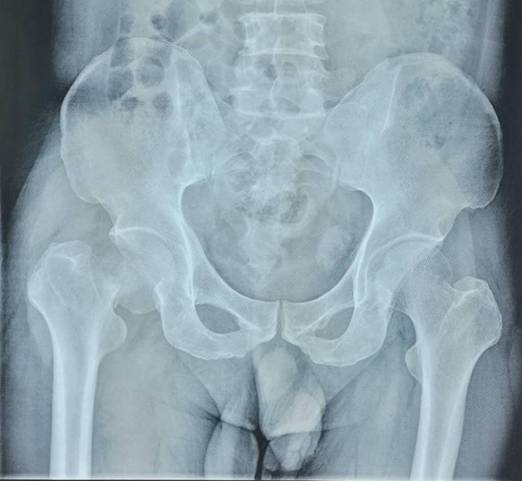

全髋关节置换术治疗股骨头坏死

优点:手术成熟,疗效确切。

全髋关节翻修术